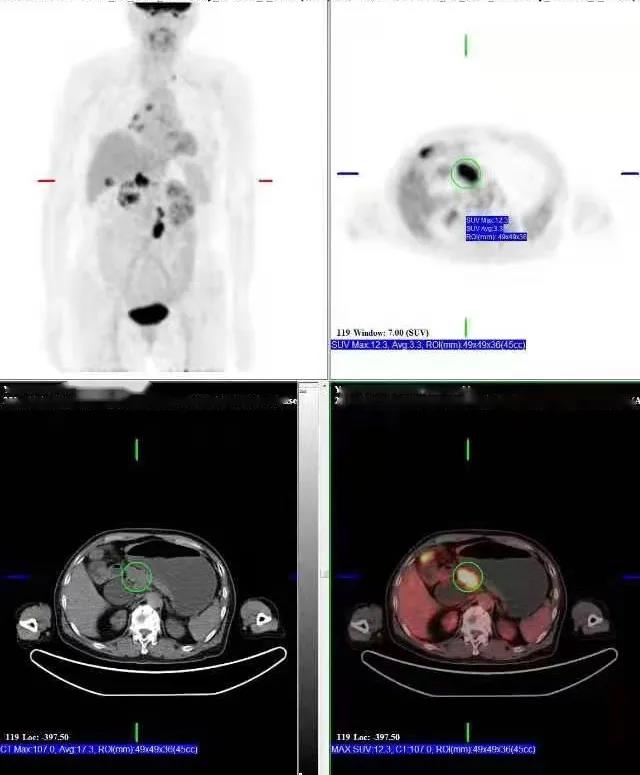

PET/CT檢查所見(jiàn):胰腺鉤突見(jiàn)一低密度灶,動(dòng)脈期及靜脈期強(qiáng)化稍低于周圍正常胰腺組織,延遲期掃描病灶與正常胰腺呈等密度,病灶邊界欠清晰,大小約2.6×3.7cm,F(xiàn)DG攝取增高,SUVmax:9.8。胰周脂肪間隙清晰,胰管未見(jiàn)擴(kuò)張。肝門區(qū)及腹膜后見(jiàn)多發(fā)腫大淋巴結(jié)影,增強(qiáng)掃描呈環(huán)形強(qiáng)化,最大者大小約2.2×3.5cm,F(xiàn)DG攝取增高,SUVmax:17.0。膽總管明顯擴(kuò)張,呈囊狀改變,最寬處約直徑4.5cm。

提示: 胰腺鉤突病變,糖代謝增高,考慮胰腺癌可能性大

肝門區(qū)及腹膜后淋巴結(jié),糖代謝增高,考慮轉(zhuǎn)移性淋巴結(jié)

先天性膽管擴(kuò)張